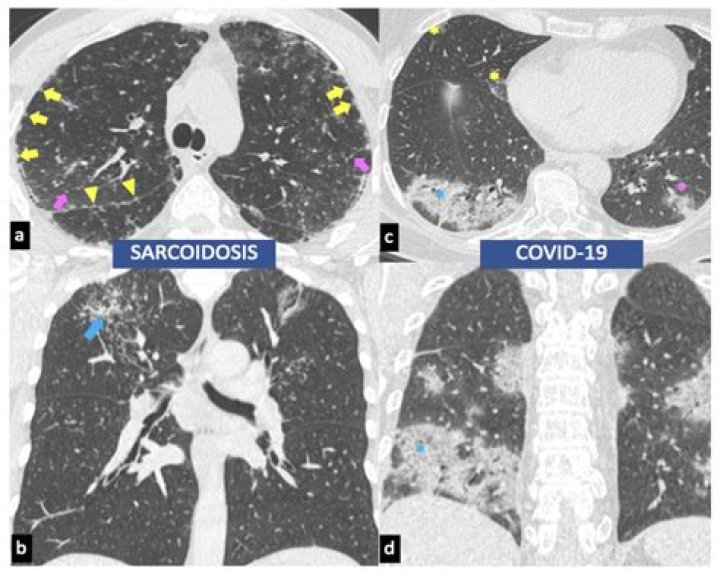

Here, we present the first case of a patient developing pulmonary sarcoidosis one year after critical illness from COVID-19. He developed numerous non-necrotizing and well-formed granulomas in mediastinal lymph nodes and pulmonary nodules, compatible radiographically and pathologically with sarcoid.